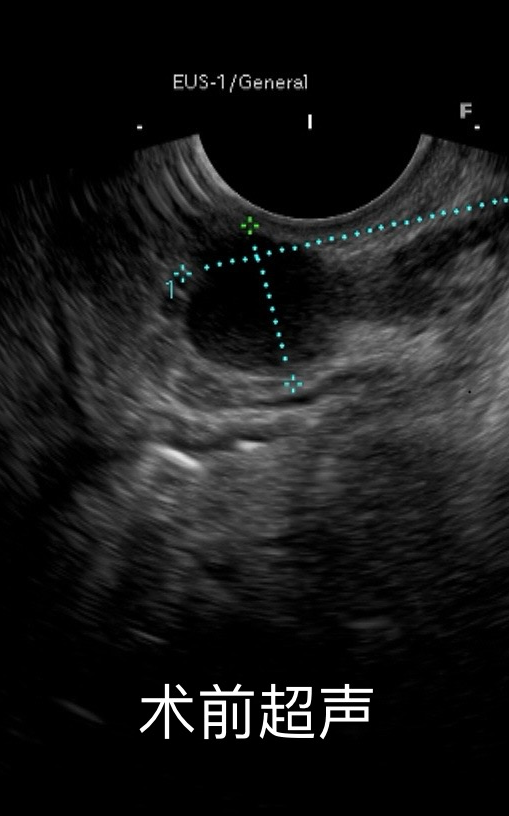

55岁男性患者莫某,因在黔南州人民医院消化内镜中心门诊行无痛胃镜检查时,发现胃底穹窿部可见一大小约3.3.cmx1.5cm的黏膜下隆后住院治疗,经超声胃镜检查提示隆起来源于固有肌层。